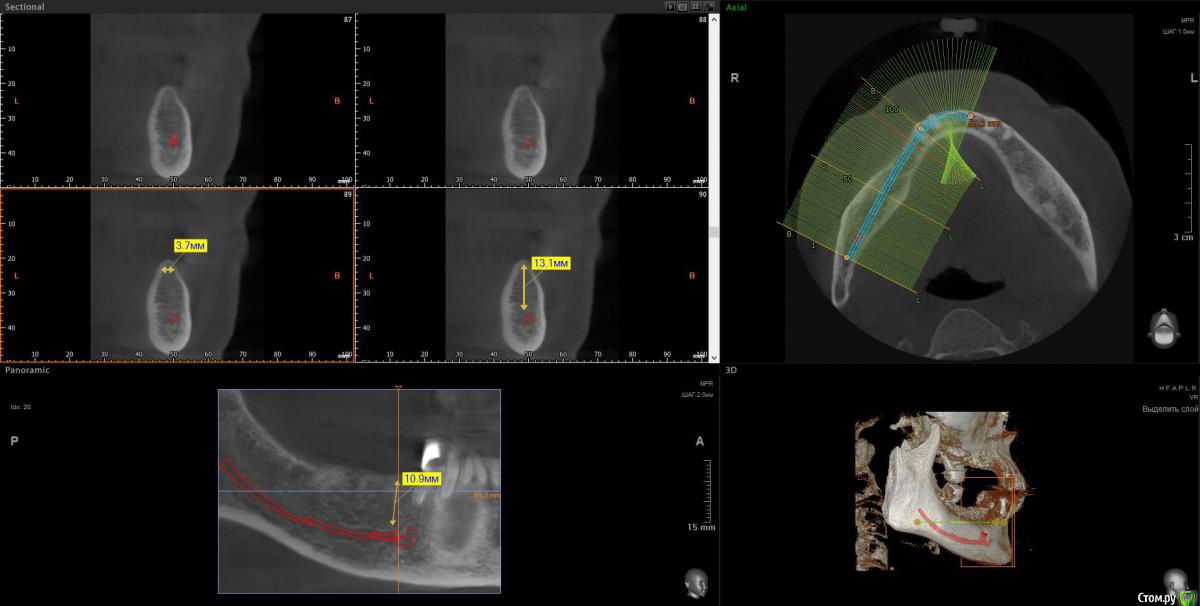

wladdX Опубликовано 11 апреля, 2018 Поделиться Опубликовано 11 апреля, 2018 (изменено) 3-й квадрант Изменено 11 апреля, 2018 пользователем wladdX 1 Ссылка на комментарий

Bier Опубликовано 11 апреля, 2018 Поделиться Опубликовано 11 апреля, 2018 ну да, последний зуб слева я бы удалил. итого 4 имплантата, синуслифтинг на в/челюсти после санации пазухи. 3 Ссылка на комментарий

Irouil Опубликовано 11 апреля, 2018 Поделиться Опубликовано 11 апреля, 2018 (изменено) Про нижнюю челюсть, слева. Левую пазуху В ЛЮБОМ СЛУЧАЕ надо оперировать. P.S. я тут так свободно про тотальное протезирование на верхней челюсти говорю, но у Вас же там передние зубы есть, простите, проглядел. Надо их состояние посмотреть, если в порядке то рассмотрите вариант который Олег Юрьевич описал - по два имплантата со стороны и мосты на них. Да, нужны будут синус лифты, но это высоко предсказуемые операции Изменено 11 апреля, 2018 пользователем Irouil Ссылка на комментарий